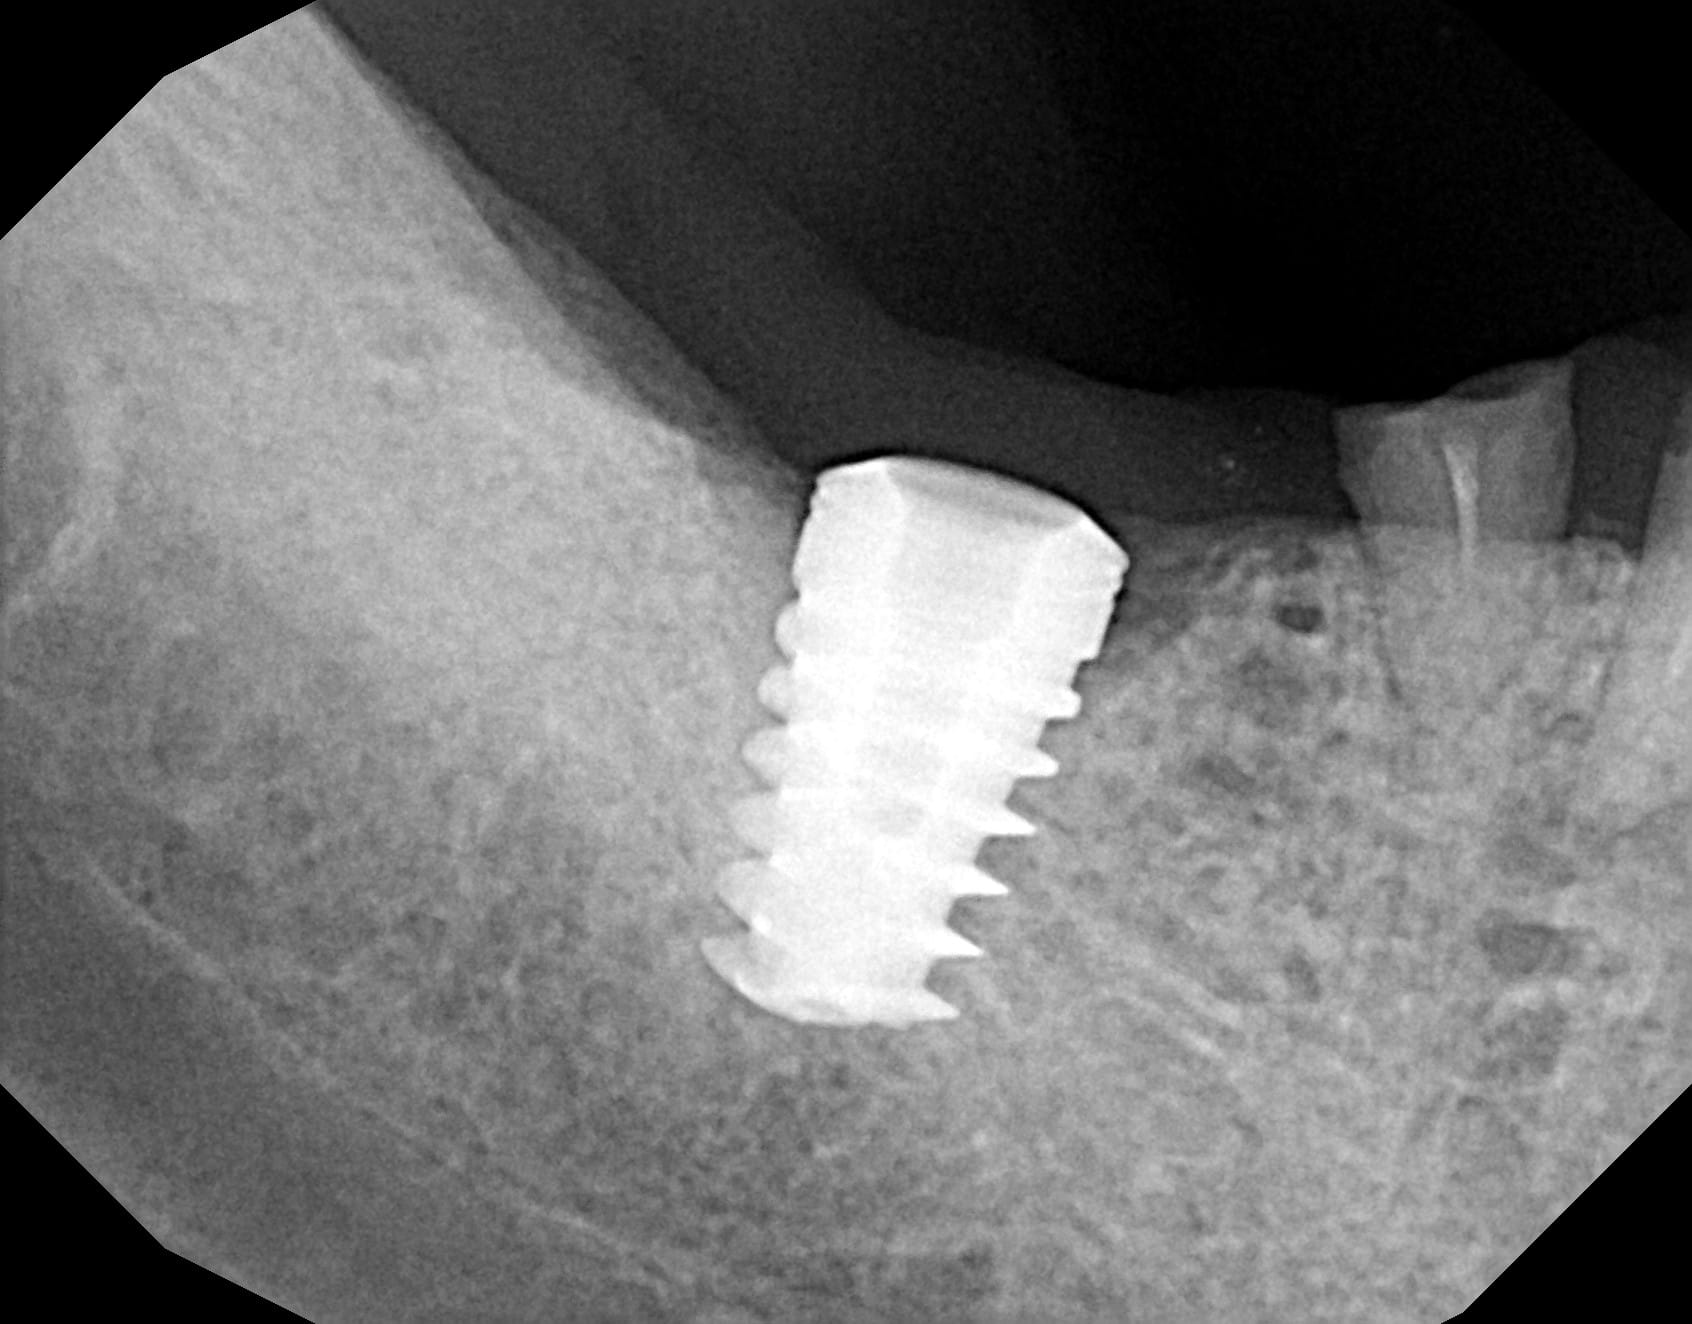

Bon, j'ai revu le patient afin de virer 46 et j'ai enfin réussi à faire une meilleure radio, visiblement, il est bien déporté en lingual cet implant

vu ce que tu me dis sur la position très linguale....amha tu auras meilleur compte de le virer (surtout qu'il a déjà commencé de cratériser au col) et d'en poser un autre....